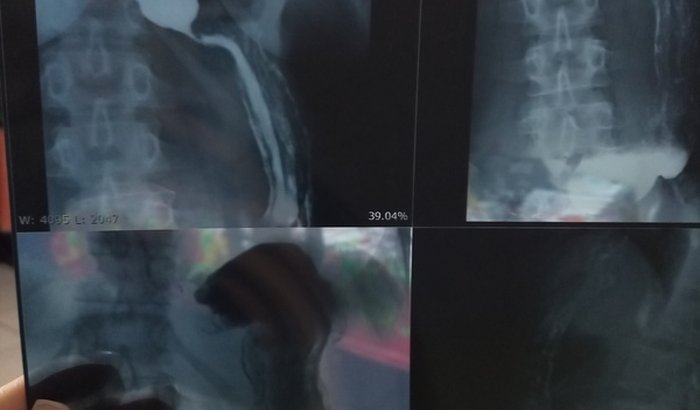

Vaquinha criada em: 07/06/2022

Deus abençoe todos, meu nome é Renata, tenho 33 anos, moro em Belo Horizonte MG, recentemente fui diagnósticada com Acalasia megaesôfago grau lll, uma doença que impede a passagem do alimento do esôfago para o estômago, causando sérios outros problemas, perdi 15 kg nós últimos meses, devido não conseguir me alimentar,  preciso fazer urgente uma cirurgia devido a gravidade da doença que tem lV estágios, eu já estou no lll, peço encarecidamente a ajuda de vocês, para eu fazer essa cirurgia e poder voltar a comer e tratar essa doença que está agravando dia a pós dia rapidamente! quem quiser saber mais sobre essa doença podem procurar meu Instagram lá tem os laudos e  falo mais a respeito da doença! desde já agradeço com muito carinho todos vocês! @renata4452020